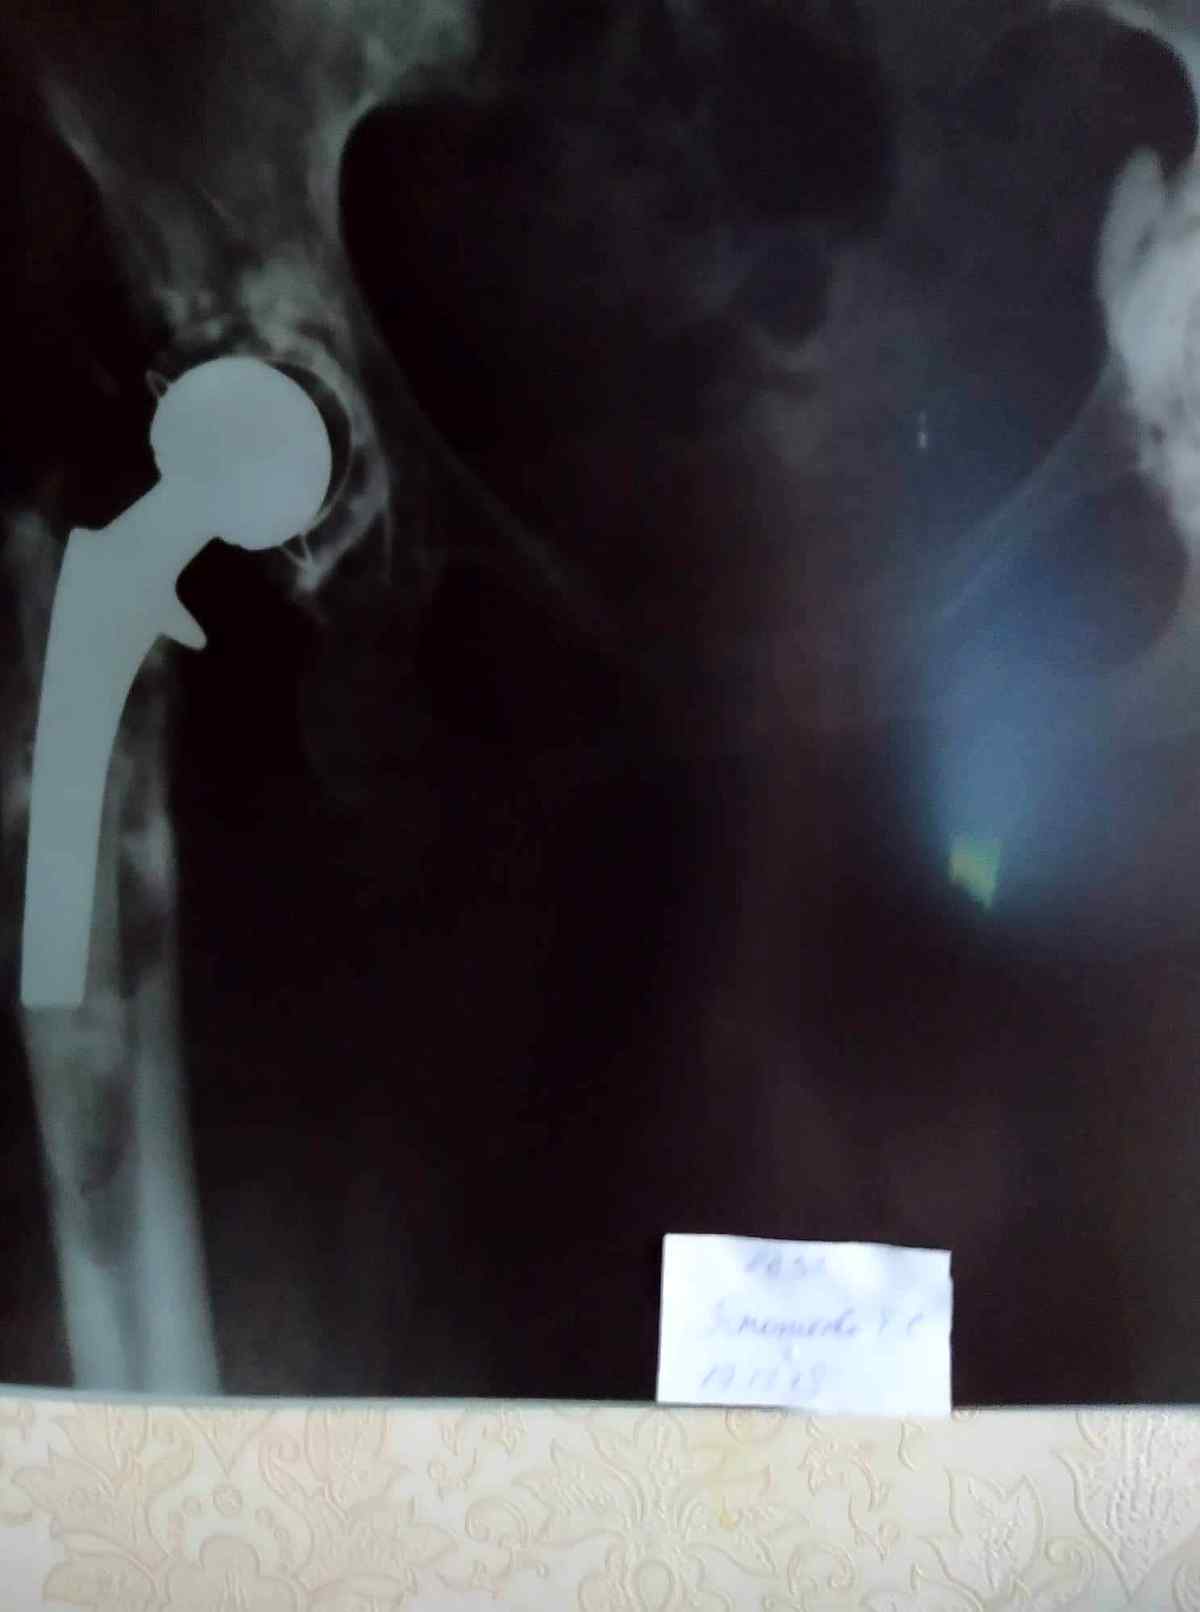

Вінничанка терміново потребує грошової допомоги на заміну ендопротеза тазостегнового суглоба. У Тетяни Ігнатьєвої закритий перелом правої стегнової кістки, нестабільність тазового ендопротезу правого кульшового суглобу. 14 років тому їй робили цю операцію, цього року потрібно знову. Сьогодні вона немає змоги її оплатити, повідомляє Vlasno.info.

17 грудня Тетяна Ігнатьєва зробила рентген. З отриманих знімків лікарі сказали, що необхідно робити терміново операцію, яка коштує від 100 тисяч гривень. Ця сума є великою для родини жінки.

– Мама зараз вдома, ходить на милицях. Якщо мама зараз буде ходити без милиць, то повністю переламає ногу. Тому що крім заміни протеза, їй необхідно ставити хомут на кістку, щоб зміцнити її. Ендопротез ставится на цементі, цей цемент зруйнував і зламав її кістку. Тому операція буде складною, – каже Саша.